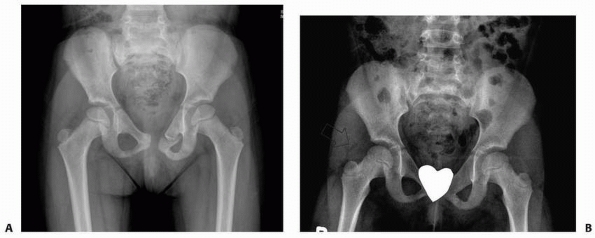

![]() |

FIGURE 20-9 A. Nondisplaced fracture through the left ischium and contralateral pubic ramus fracture. B.

Follow-up radiograph shows mild displacement and incongruity of the acetabulum and complete healing of the superior pubic ramus fracture. Either displacement of the fracture fragments or premature closure of the triradiate cartilage could have contributed to the incongruity of the femoral head in the acetabulum. |